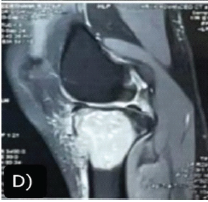

A Rare Case Report of Advanced Surgical Management of Proximal Tibia Giant Cell Tumor in a 20-year-old Girl-Extended Curettage and Sandwich Technique

M Harishkumar , B Mohan Choudhary , Arjun Ganesh , Kevin Lourdes

………………………………p.158-163